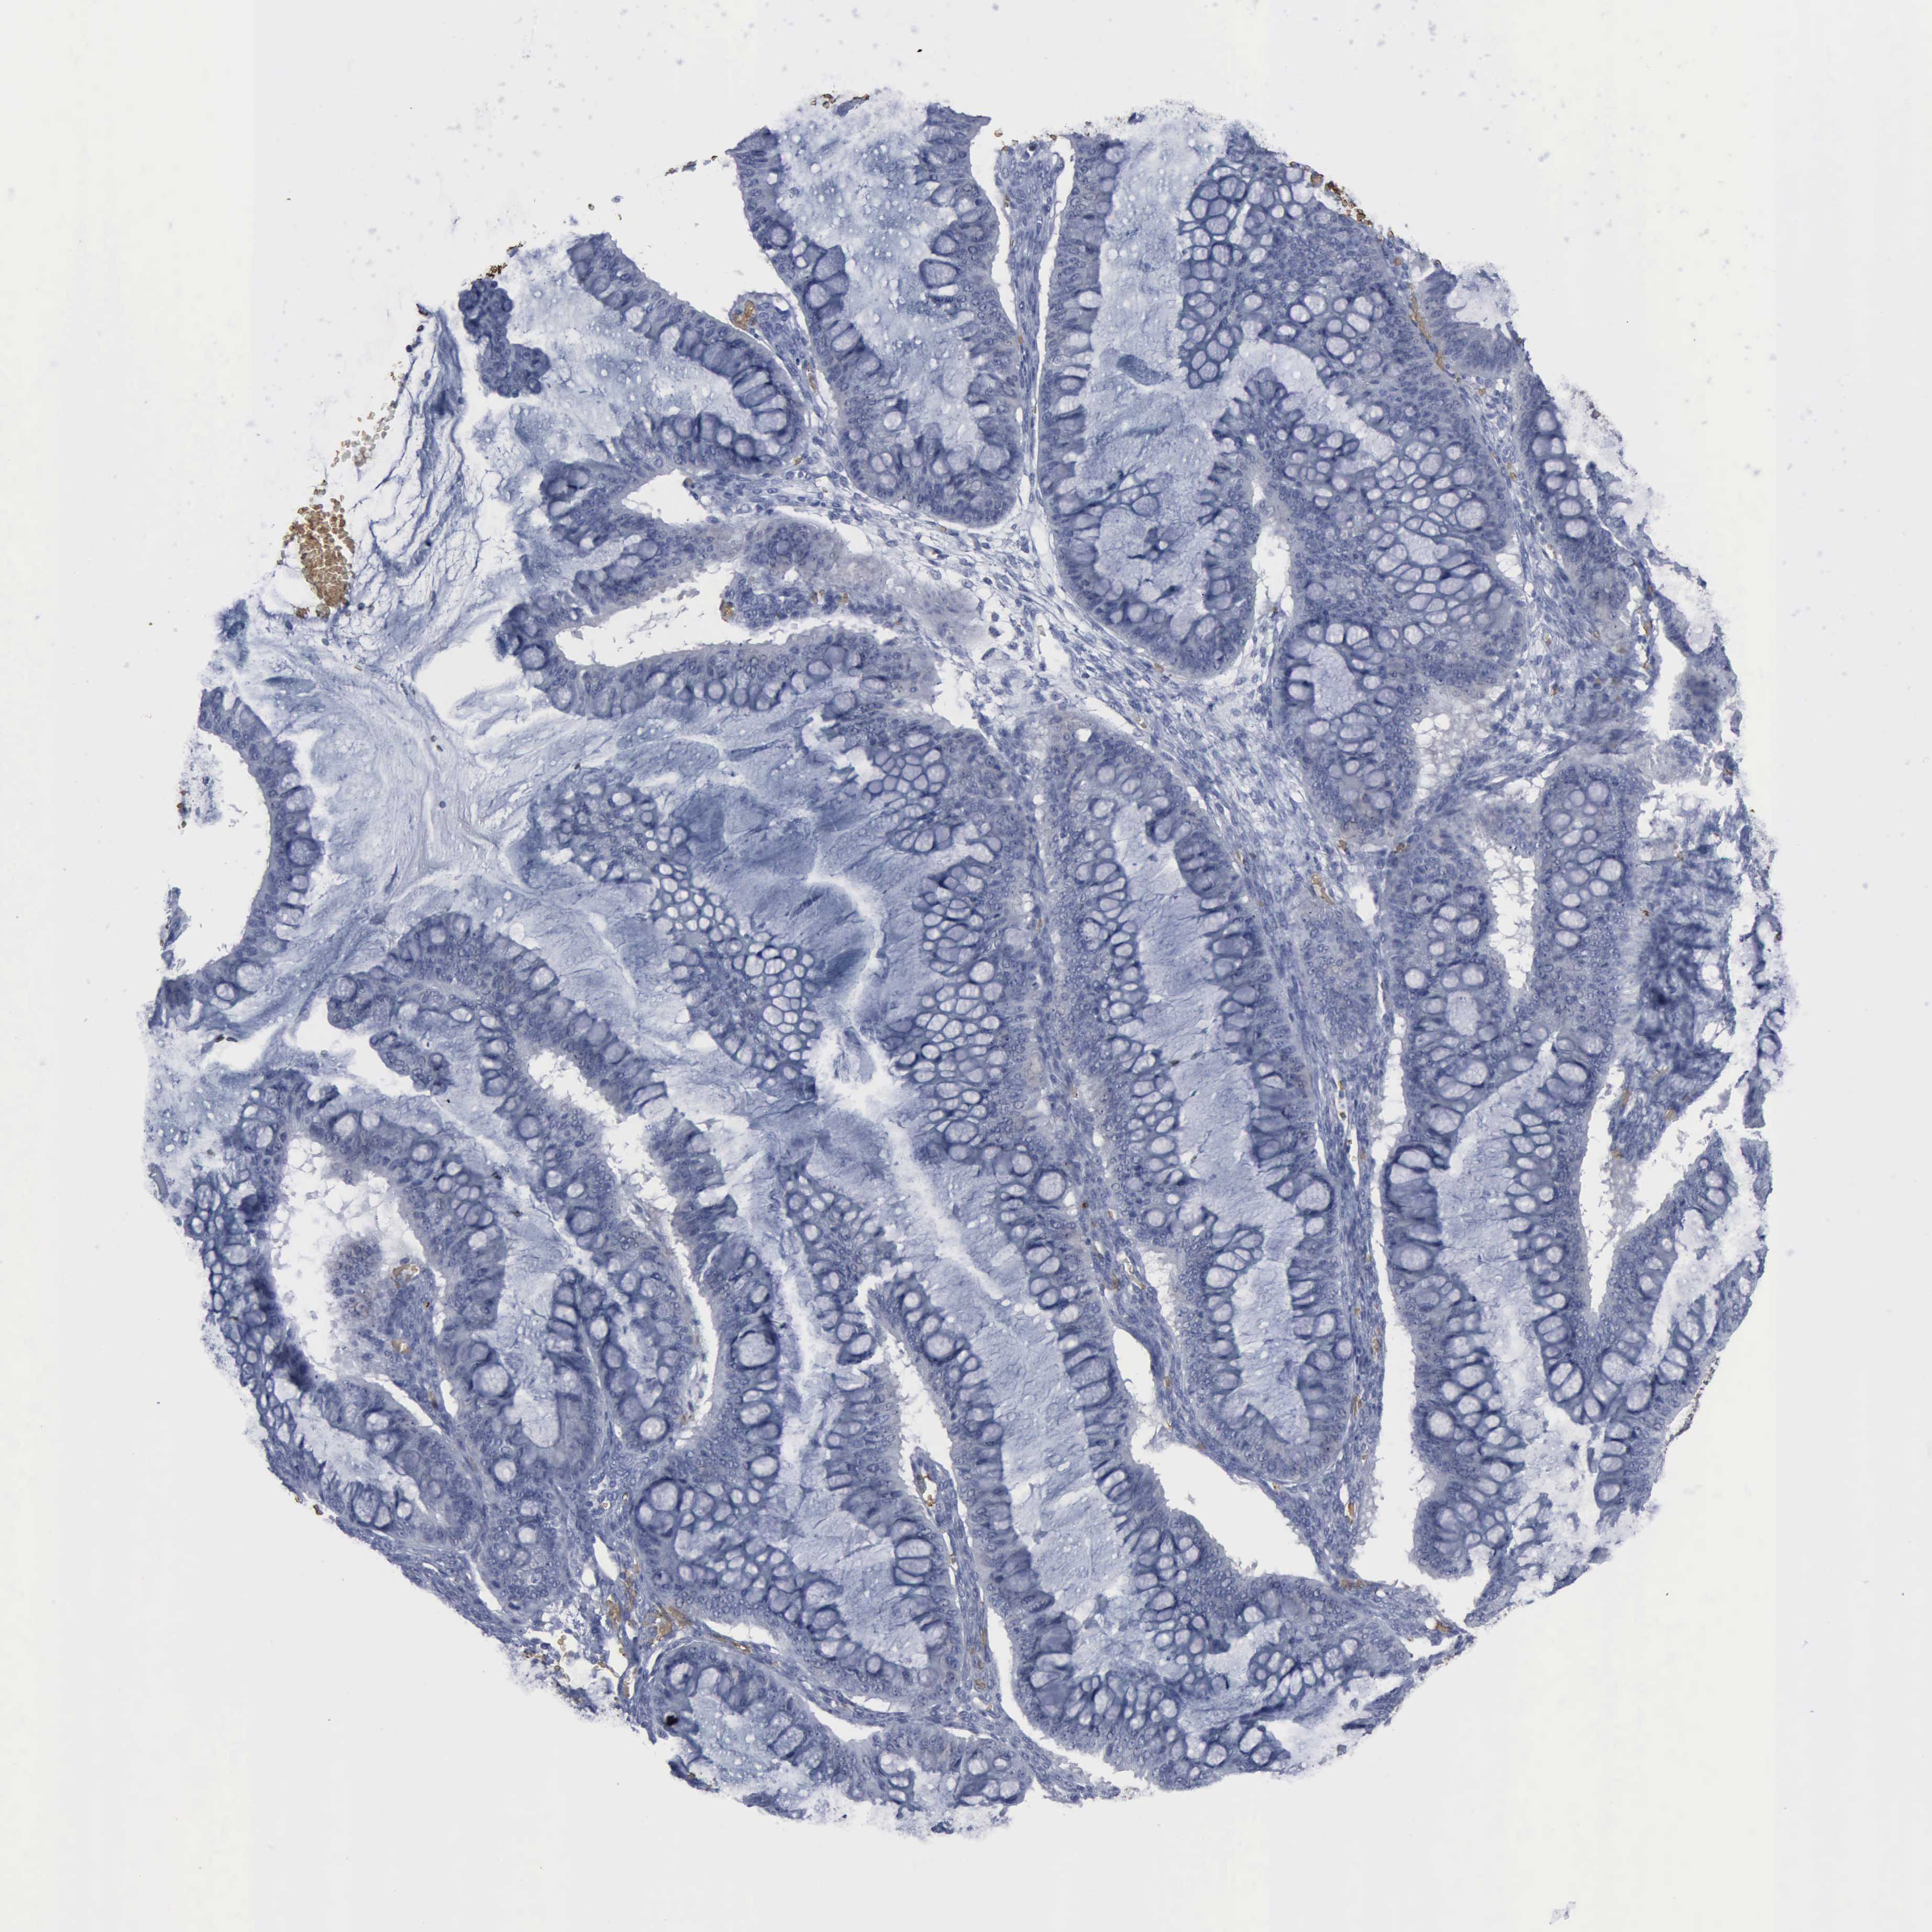

OVARIAN CANCER - Protein expressioni

A mouse-over function shows sample information and annotation data. Click on an image to view it in a full screen mode. Samples can be filtered based on level of antibody staining by selecting one or several of the following categories: high, medium, low and not detected. The assay and annotation is described here.

Note that samples used for immunohistochemistry by the Human Protein Atlas do not correspond to samples in the TCGA dataset.

Antibody stainingi

Antibody staining in the annotated cell types in the current human tissue is reported as not detected, low, medium, or high, based on conventional immunohistochemistry profiling in selected tissues. This score is based on the combination of the staining intensity and fraction of stained cells.

Each image is clickable and will lead to virtual microscopy that enables deeper exploration of all samples and also displays staining intensity scores, fraction scores and subcellular localization as well as patient and tissue information for each sample.

Antibody CAB000361

Cystadenocarcinoma, mucinous, NOS

Carcinoma, endometroid

Cystadenocarcinoma, serous, NOS